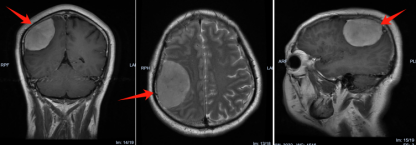

该院神经外三科主任金鑫接诊后,根据患者的病史及相关影像资料,初步诊断为右侧额顶叶功能区脑膜瘤。“由于部分肿瘤对大脑功能区造成压迫,导致患者出现左上肢麻木无力、触觉减退。如不及时手术,肿瘤继续压迫,甚至可能导致肢体瘫痪。”

术前影像检查。

2月中旬,金鑫带领神经外三科团队为患者行右侧额顶叶功能区肿瘤切除术。术中,金鑫在显微镜下小心翼翼操作,在保护周围脑部组织的同时,顺利将大小约6cm×6cm×4cm的肿瘤完整切除。“切除的肿瘤,大小、形状都和一个‘肉包子’极其相似。”术后病理结果为良性脑膜瘤。